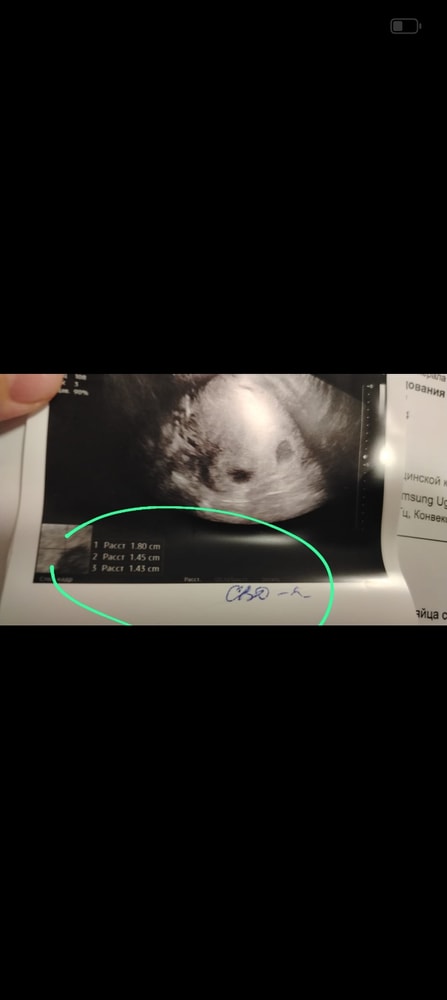

Короче сначала расстроилась, сейчас дома все на листочек выписала, пересмотрела- почему доктор из при описании перепутал... И что получается, что один из малышей СВД вырос только на 3мм за неделю, и ктр на 4мм... Что вызывает опасения...если свд выросло лишь на 3мм это приговор? Или может что то измениться в лучшею сторону?

Но есть вариант, фото прикреплю, что он их перепутал при описании эти номер 1и 2, и описал соответственно наоборот, тогда в среднем они подросли на 5мм...

Может погрешности измерения, но написал он как написал в заключении ..

Вот описание